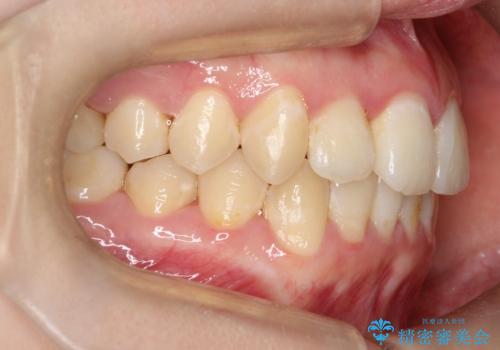

前歯が前後反対にかんでいる インビザラインによる矯正

- 前歯のがたつきを気にされて来院されました。

上顎の前から二番目の歯が内側に入り込んでおり、前後反対にかんでいる状態でした。

歯と歯の間にわずかに隙間を作り並べる計画としました。

しっかりとマウスピースを使用していただけたので、順調に治療を終えることができました。